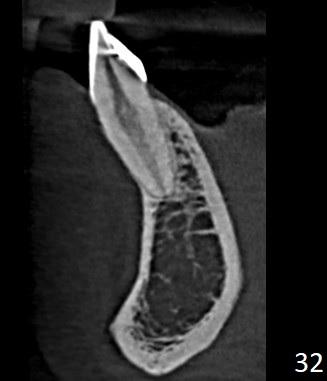

CBCT wycinkowe żuchwy.

Ząb 31 położony przedsionkowo w stosunku do szczytu części zębodołowej żuchwy.

Podejrzenie dehiscjencji wzdłuż przedsionkowej ściany korzenia zęba.

Cienki fenotyp obserwowany również przy zębie 41.